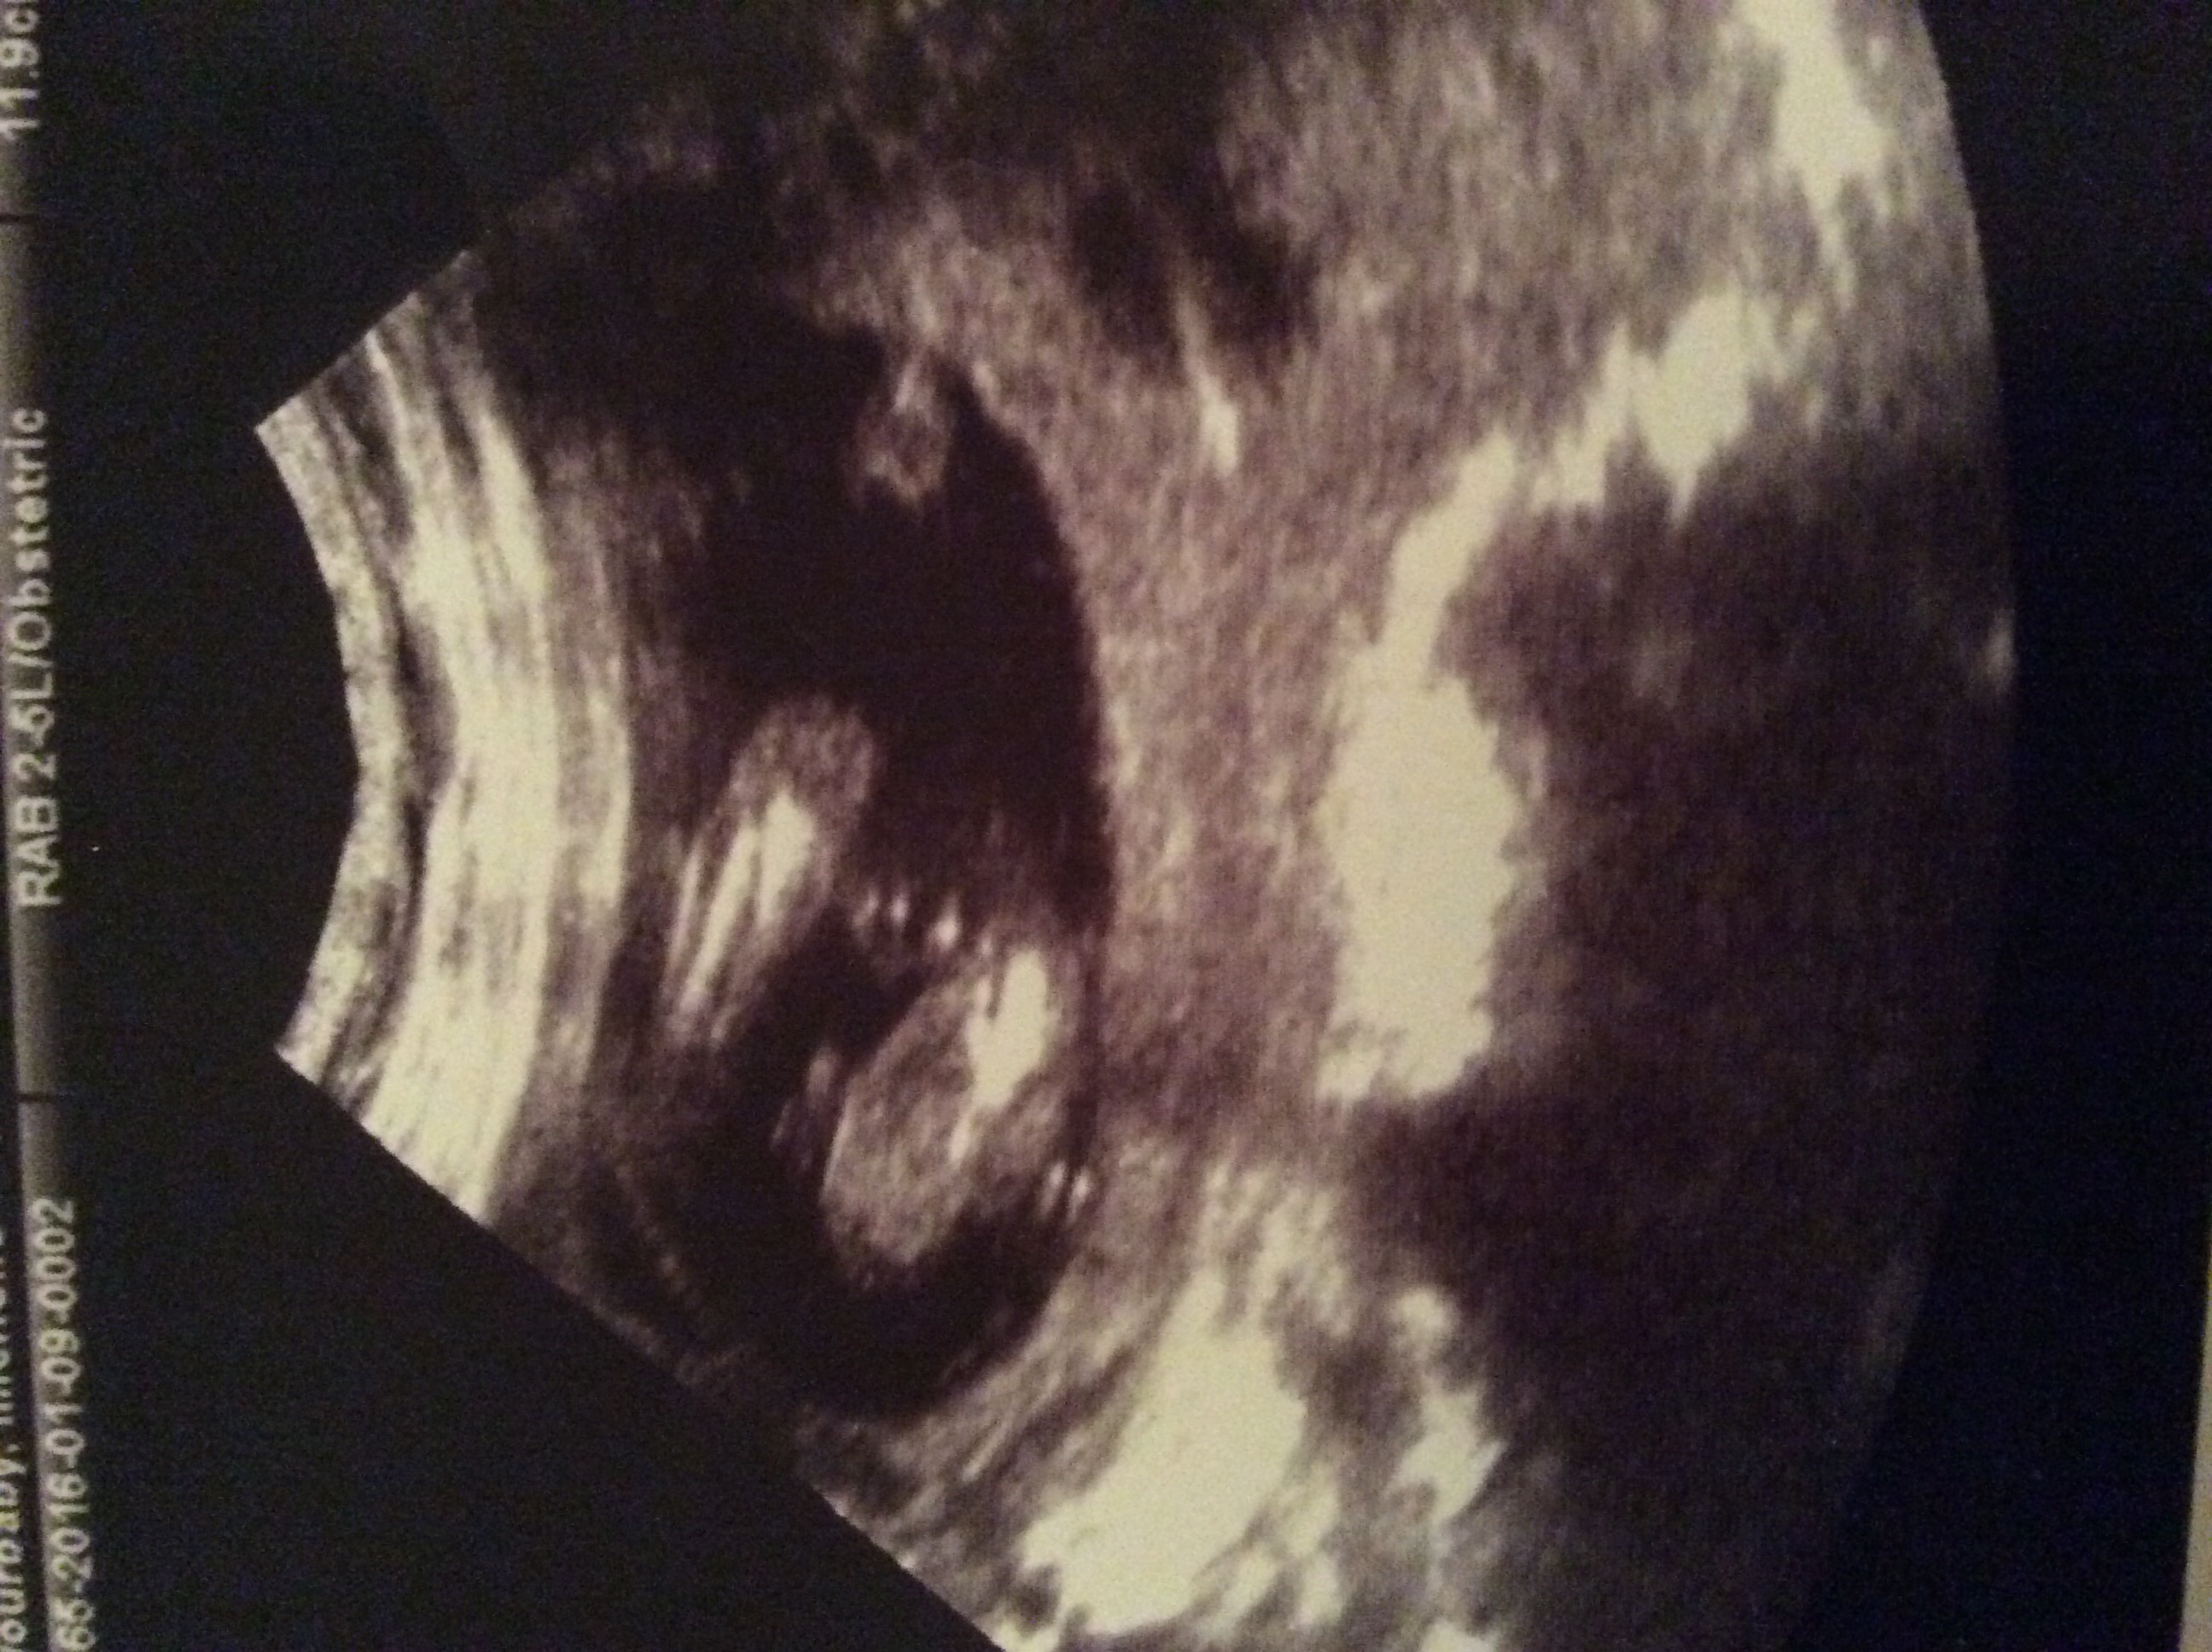

Potty shot taken at 16 weeks, what are your guesses?

I say a girl [emoji4]

Looks girly but really not a great shot. Was the tech confident about gender?

Yeah, she was pretty confident I'd say. I didn't really ask her how confident she was as I already had another scan booked for 20w, so knew I could get it confirmed then. Or not!

Girl

The tech saw more than this one shot, so that's much more reliable than us guessing on this one!